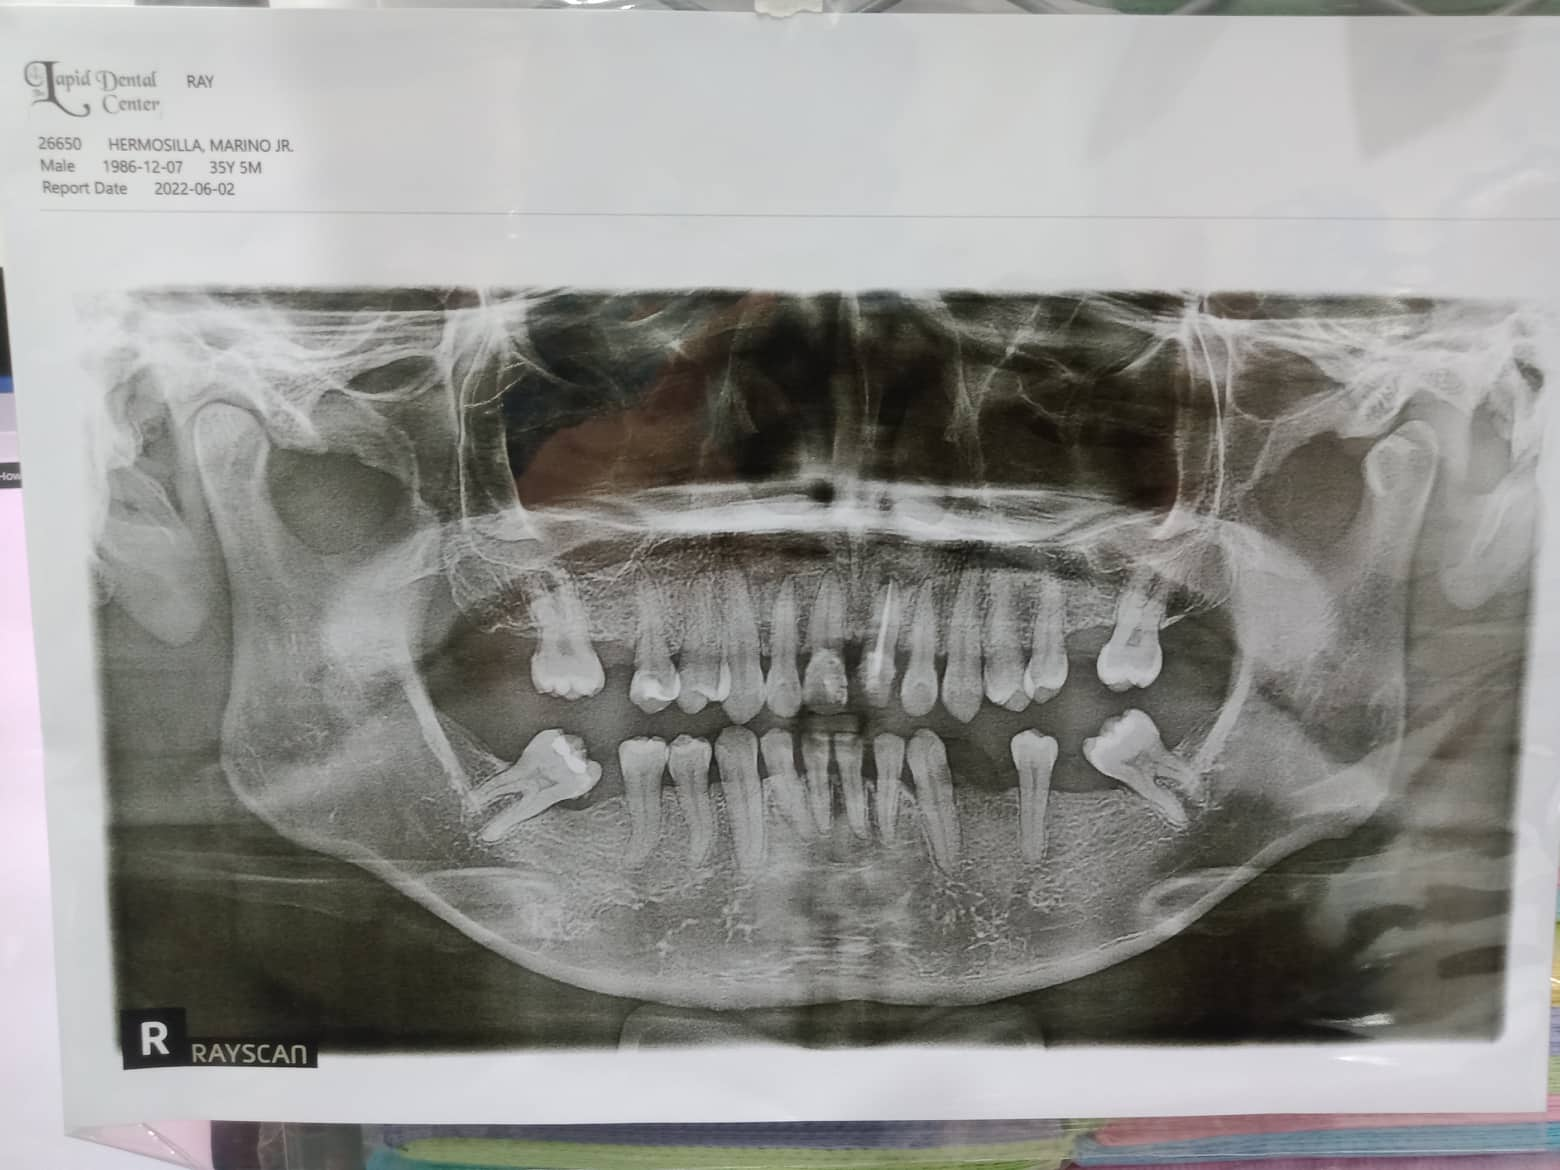

- Procedure